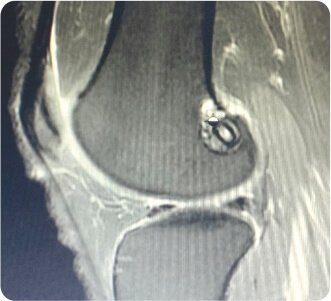

New Anterior cruciate ligament Graf

X-ray showed no fractures. The Femoral tunnel was noted to be in an abnormal position. MRI showed complete ACL and medial meniscus posterior horn tears. The patient was planned for revision arthroscopic anatomic ACL reconstruction +/- medial meniscus surgery. During arthroscopy, significant laxity of the ACL and partial tear of posterior horn of medial meniscus were noted. The hamstring graft was harvested from the contralateral knee, as the ipsilateral graft was harvested during the index surgery. The graft was augmented with FiberWire for internal bracing. Old ACL remnants were cleared with a shaver. Loose pieces of old femoral BioScrew were removed. Partial medial meniscectomy was done and trimmed to stable borders. New femoral and tibial tunnels were made. Anatomic ACL Reconstruction was done and stabilised with Arthrex Tightrope RT on femoral side and BioComposite screw on tibial side. Final stability showed negative anterior drawer test. The next day, he was mobilised with full weight-bearing walking. On follow-up, he achieved full range of movements and returned to normal sporting activities.